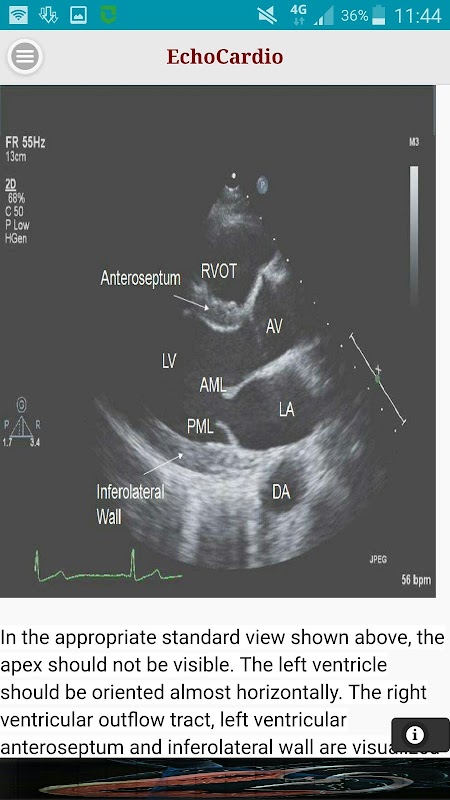

Paraesternal longo eixo